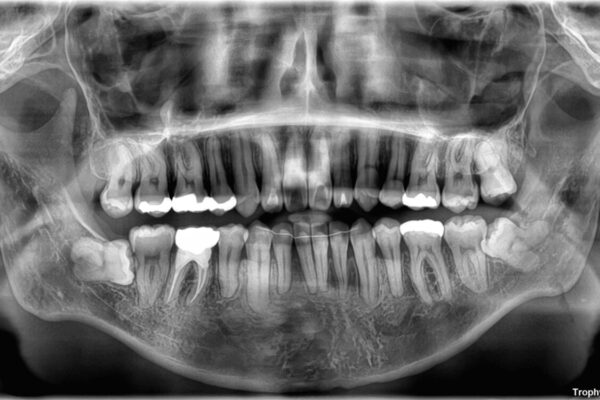

精密検査の結果、上下左右の小臼歯4本を抜歯し、そのスペースに前歯を後方へ移動させる矯正治療をご提案しました。

治療前

• 口元の突出感を改善!目立ちにくいワイヤー矯正で自信を持てる自然な横顔に 治療前画像